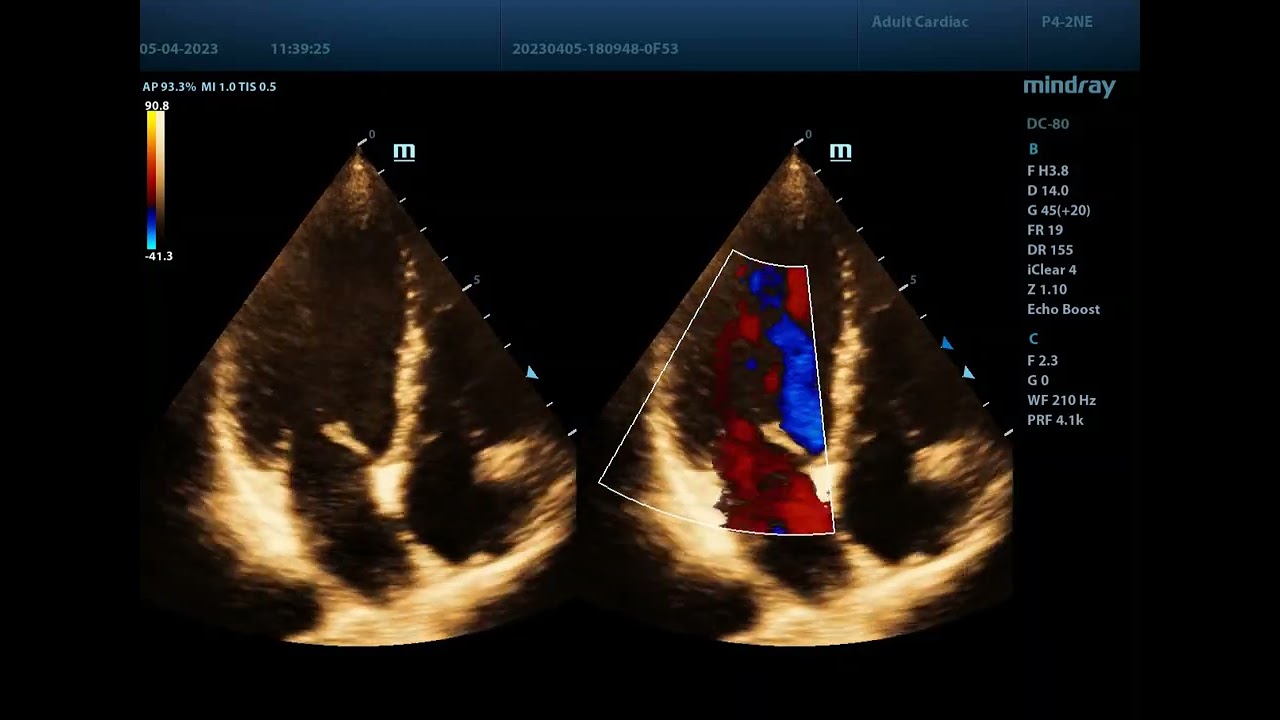

Dual Live - одновременное отображение серошкальной картины и цветовой карты

В ежедневной работе врача ультразвуковой и функциональной диагностики случаются ситуации, когда картина цветопотоковой визуализации закрывает собой нюансы серошкального ультразвукового изображения. При этом осмотр отдельно серошкальной картины не позволяет четко представить себе, как с ней взаимодействует цветной допплер и как идут потоки крови.

Компания Mindray решила эту проблему в своих приборах с помощью функции Dual Live. Она позволяет одновременно осматривать серошкальную картину и цветовую карту. Функцию можно найти как в проверенных временем моделях, например, Mindray DC-60 Pro или Mindray DC-70 Pro, так и в новых приборах серии Mindray Resona.

На видео функция Dual Live в действии, экран прибора Mindray DC-80 X-Insight.